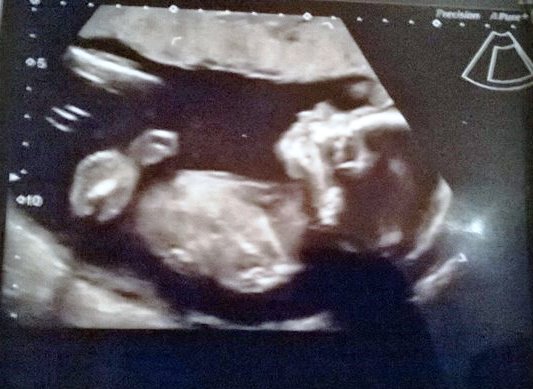

She's a girl! Not what most of you thought, but they thought she was at 16 weeks when my consultant scanned me, and yesterday at 20+4 they said it's as near to definite as it's possible to be, so here she is in her 20+4 glory!

Attachment 24699